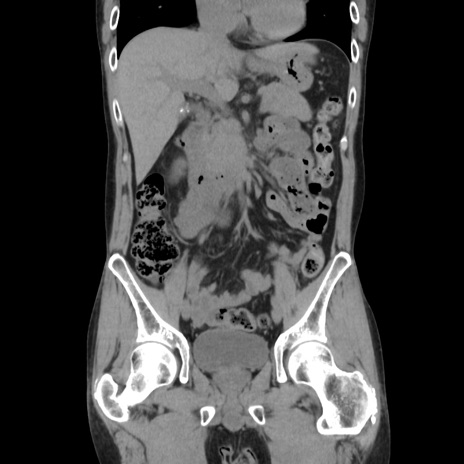

症例37(冠状断像)

【症例】40歳代 男性

【主訴】腹痛

【現病歴】4時間ほど前に電車に乗車中に臍部上より腹痛出現。徐々に増悪し起立困難となり、救急外来受診。生ものは数日食べていない。今朝お雑煮を食べた。

【身体所見】BT 36.8℃、BP 117/84mmHg、HR 91/min、SpO2 97%、苦悶様、腹部:臍上部広範囲圧痛あり、反跳痛±

【データ】WBC 8100、CRP 0.03